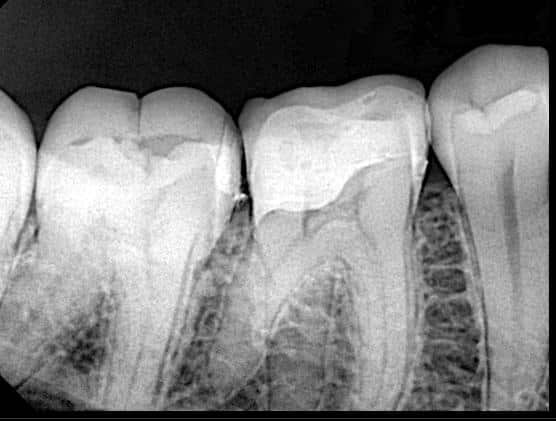

After D.M.E

Post operative x ray , you can see the fitness

The biobase now completed , just need finishing and polishing, the mesial box of the second molar restored with direct composite

Biobase ready